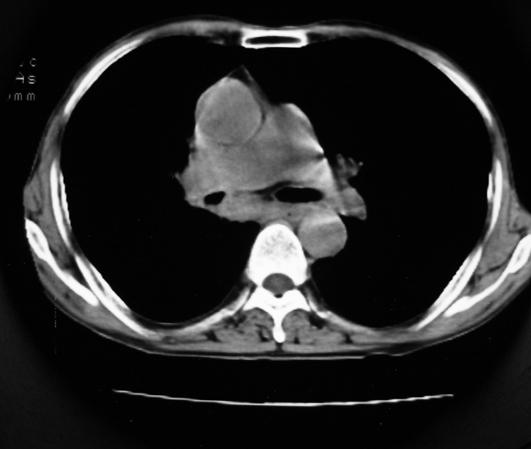

以下是引用同在2007-1-27 14:13:00的发言:[br]支持右侧中央型肺癌伴阻塞性病变.

以下是引用zjzjr在2007-1-27 16:56:00的发言:[br]支持右肺中心型肺癌伴阻塞性肺炎.